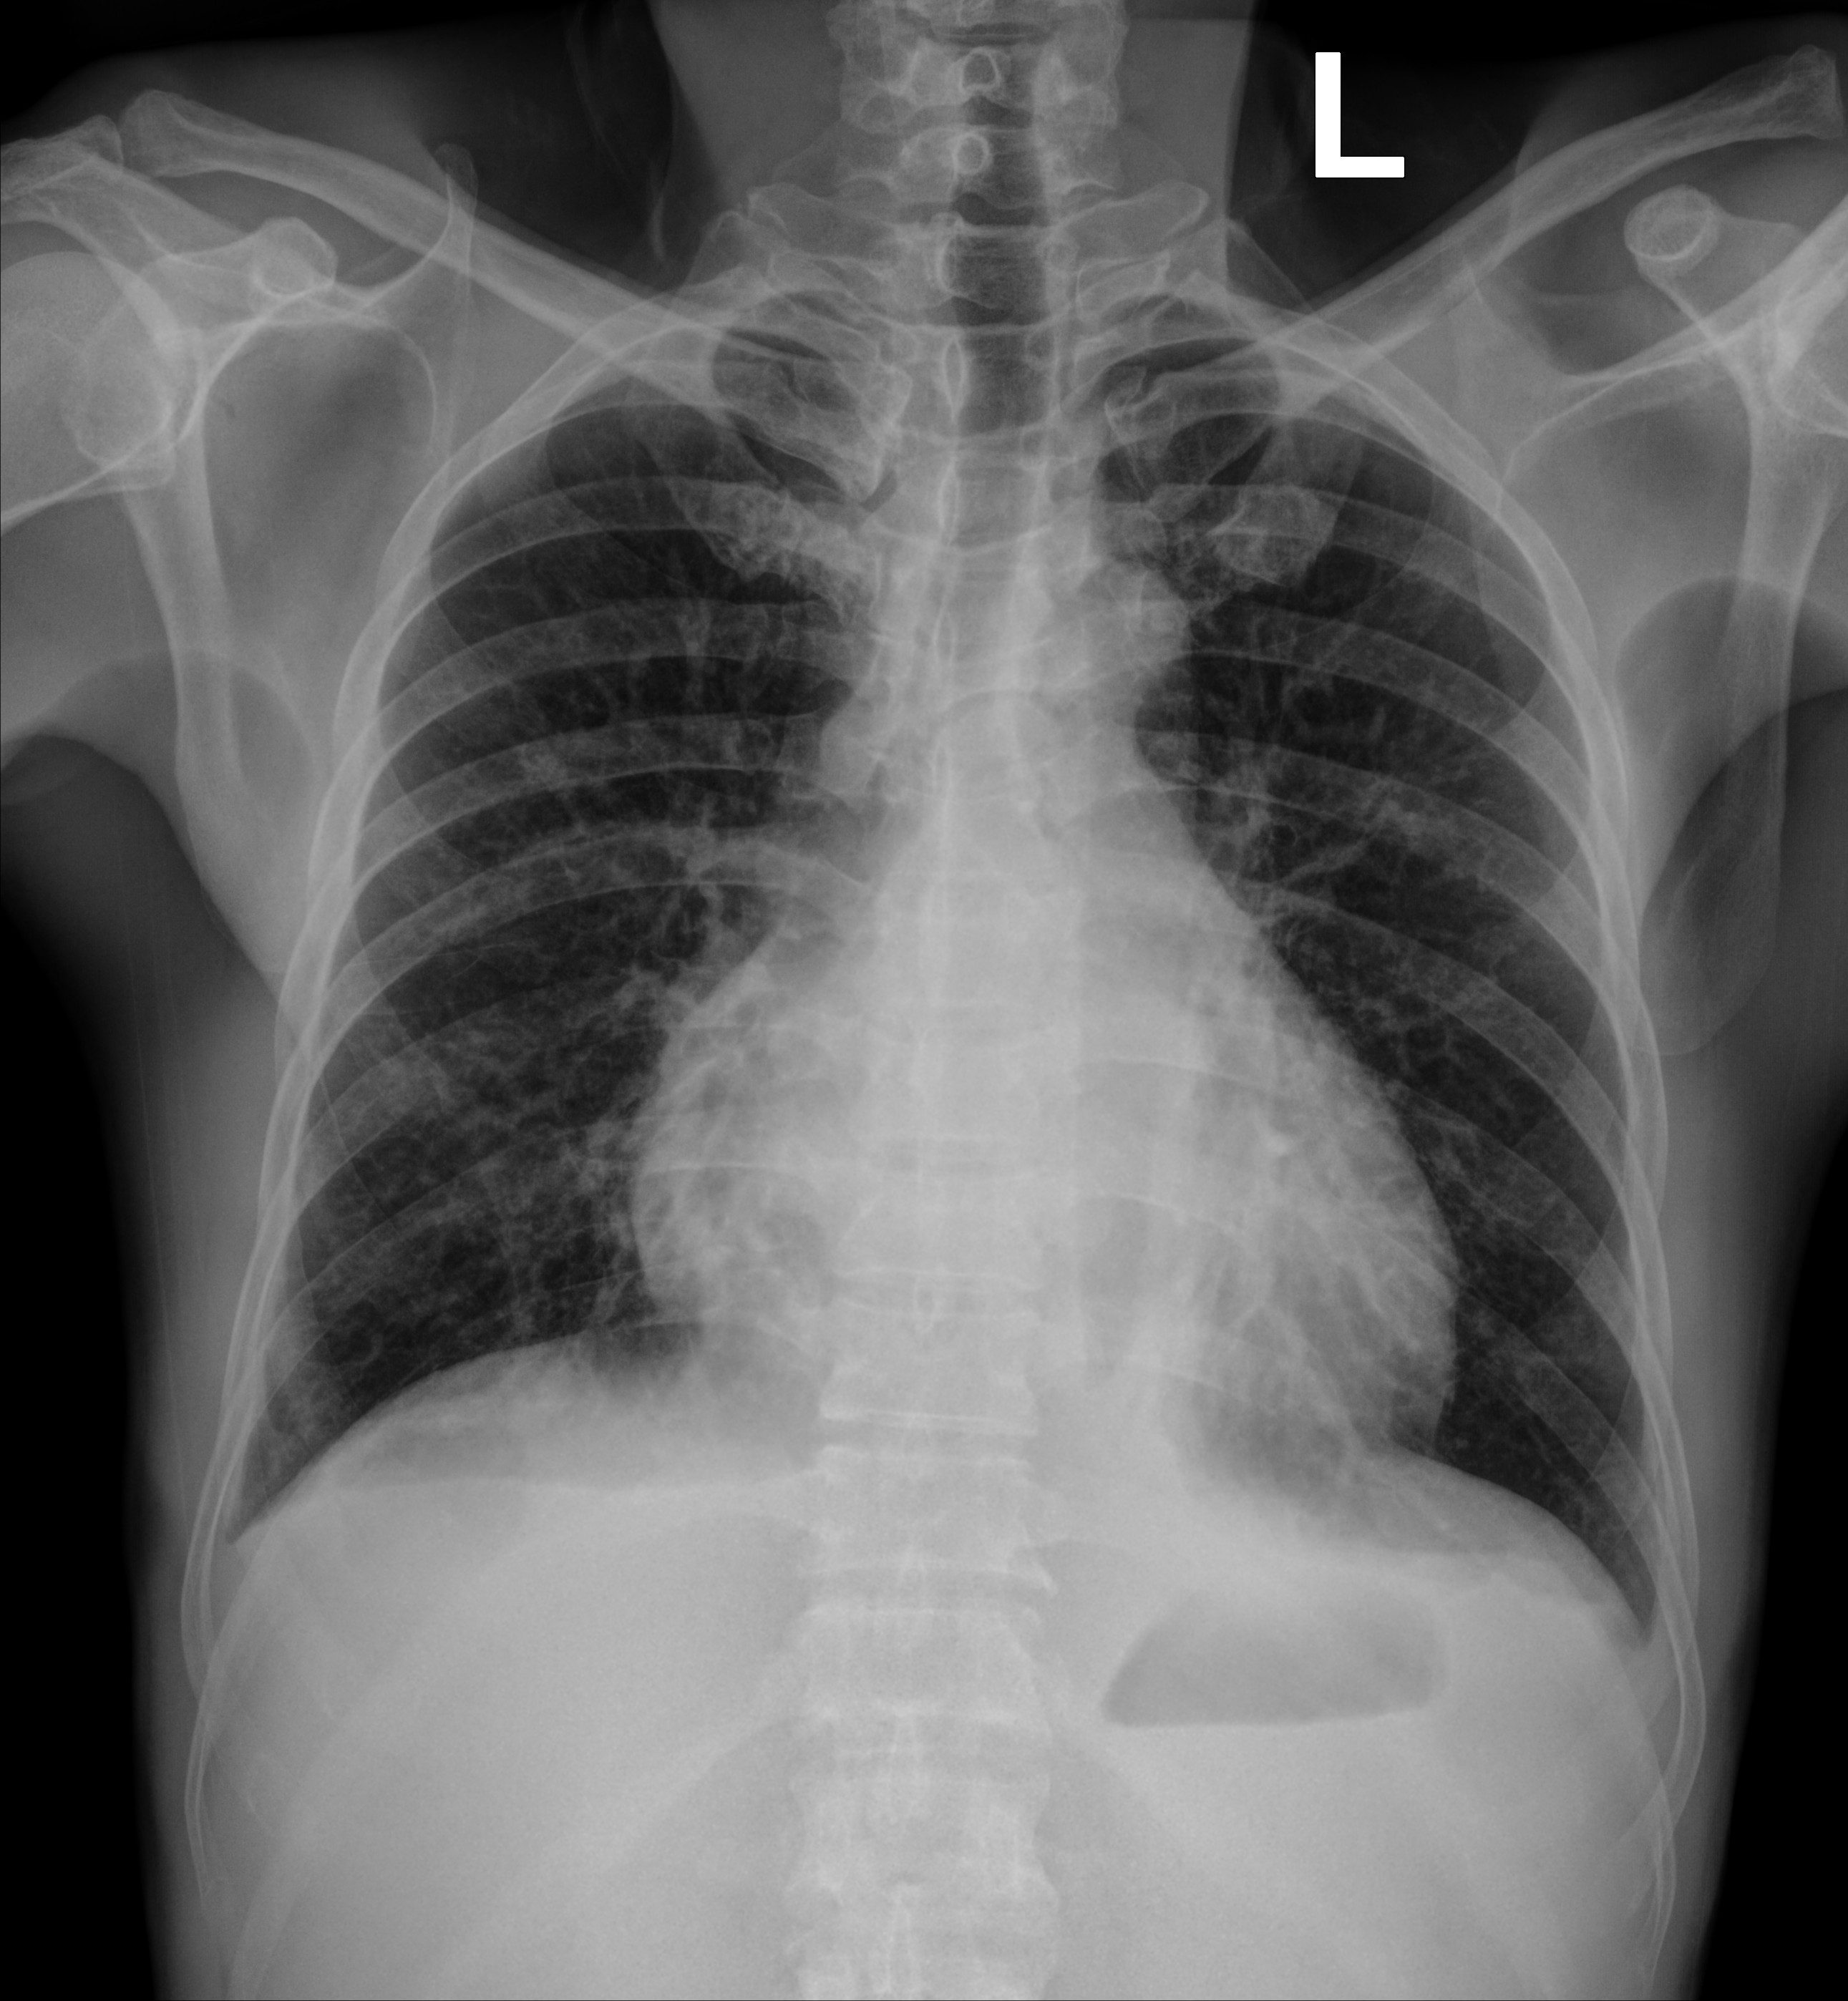

Bệnh nhân Chu Đ.C., nam 52 tuổi, quê Phú Thọ, được chuyển xuống Bệnh viện Bạch Mai ngày 20/10/2025 vì chảy máu mũi nhiều, điều trị tuyến trước không dứt. Vào viện, người bệnh được làm xét nghiệm máu và tủy, được chẩn đoán Bệnh bạch cầu cấp dòng tủy (AML-M6) kèm nhiễm trùng tiết niệu, rối loạn đông máu. X-quang ngực chụp buổi sáng cho thấy hai trường phổi sạch, tràn dịch màng phổi nhẹ, nghĩa là phổi lúc đó hoàn toàn “trong”.

Ảnh: Phim chụp Xquang phổi của bệnh nhân C.Đ.C (21/10) và CT scan (24/10)